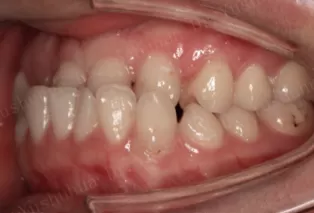

Intraoral photos